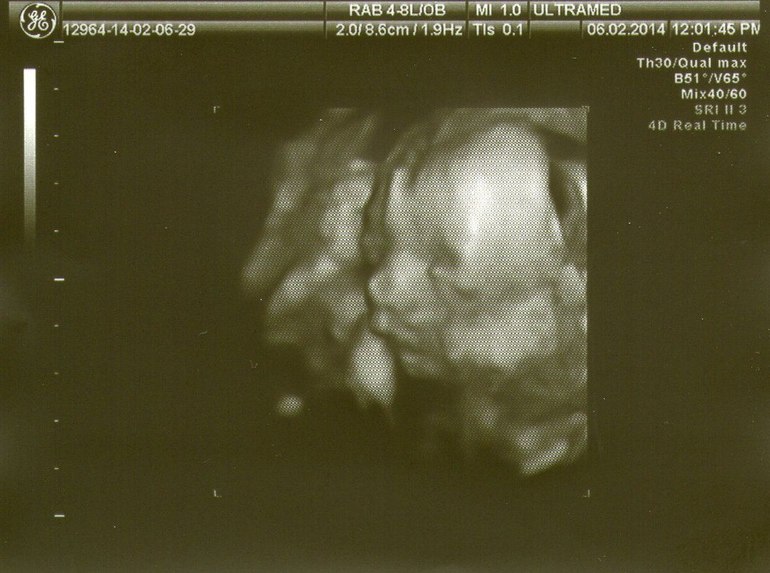

Ходили мы на 2Д,но тетя врач решила нас немного побаловать и показала Матвейку и в 3Д

Профиль у нас сразу видно папашкин!Сравнила фотки старшего и младшего в 3Д,такие разные,хотя я думала что на таком сроке все одинаковые!